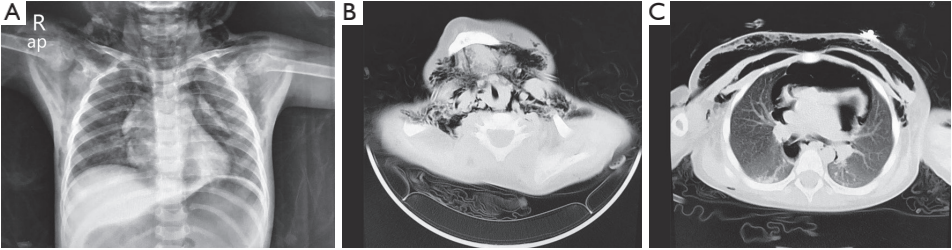

大约4小时后,患儿哭后出现烦躁和发绀。急诊胸部X光检查显示双侧颈部和胸壁有皮下气体,并有纵隔气肿的可能性(图1A)。立即通过鼻插管给氧,并使用14号针头进行皮下排气。进一步的计算机断层扫描(CT)显示右肺上叶和双肺下叶轻度炎症,颈部和双侧胸壁皮下气肿,以及纵隔气肿(图1B、1C)。密切观察了患儿的病情变化。

图1. X线和CT扫描分别显示皮下气肿和纵隔气肿